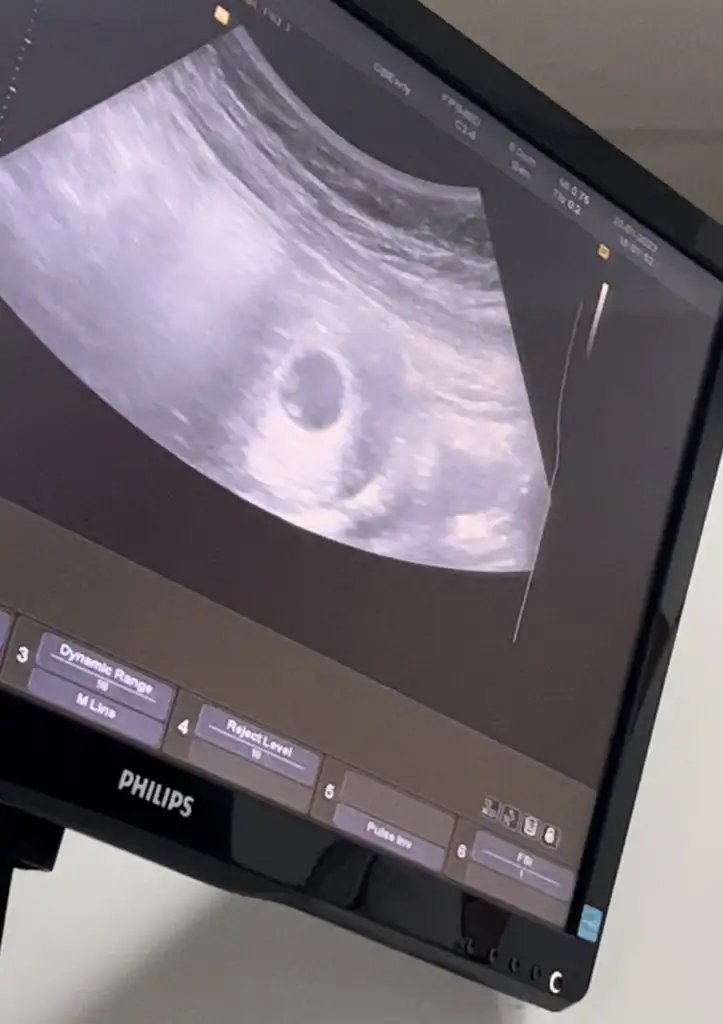

Tek yumurta ikizi mi canımYaaa çok teşekkür ederim bayadır tedavi sürecindeydim ister istemez tedirgin oldum ama çok teşekkür ederimilk önceliğim sağlıklı olması gebeliğin ikiz diyince bi şok geçirdim birde hiç bilgim olmadığı için benim de tek kese göründü ultrasan burdaki gibi ilk gebelik acemilik işte nası oluyo bilmediğim için dedim normal gebeliklerde de kese de böyle iki beyazlık mı görünüyor Eki Görüntüle 3197859 Eki Görüntüle 3197860

Tek kese göründü ama ikiz mi daha belli değil tek kalp atışı göründü ikizlerde kalp atışları sonra mı oluyo hiç bir bilgim de olmadığı içinTek yumurta ikizi mi canım

İkiz olabilir belkide silik çıkmamış gayet net :))